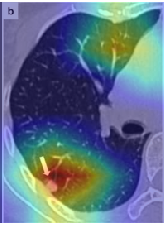

In order to make our models more transparent and provide detailed visual analysis, we present the Grad-CAM localization maps obtained by different models. We consider CT images with COVID-19 abnormalities from the test set of each dataset and highlight the important regions considered for the prediction. For the SARS-CoV-2 dataset we use the Inception V3 model. Figure 13 shows the original CT images and their localization maps. Our model is capable to detect regions that show abnormalities in the CT scans.

A wide variety of typical and atypical CT abnormalities have been reported for COVID-19 patients in various studies [58, 59]. So, we tested our models on external CT images extracted from these two publications as they feature typical findings of COVID-19 pneumonia marked by specialists. In order to make sure that not any of the extracted images are unintentionally included in our datasets, specifically the COVID19-CT dataset, we use the model trained on the SARS-CoV-2 dataset. First, the InceptionV3 model is employed to classify the extracted CT images. The model is able to correctly classify the given CT images as COVID-19. Second, in order to interpret the model’s generalization capabilities, we apply the Grad-CAM technique to visualize the regions of abnormalities that are considered. By assessing the different CT images in Figure 15, we can see that the model accurately localizes the disease-related regions. Even more interesting is the fact that the model ignores any specific marks in the images like letters and only localizes the COVID-19 related regions. These visual explanations show the success of our models to learn relevant, generic visual features related to COVID-19 and are capable to correctly classify CT images outside the datasets on which they are trained.